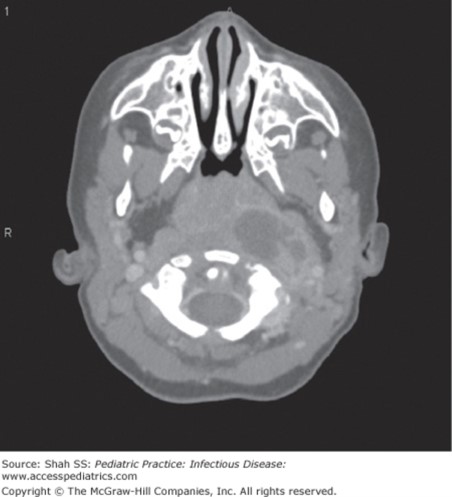

The correct answer is “C.” This patient has a retropharyngeal abscess. Younger children often present with a preceding history of viral URI symptoms while an older patient usually has a history of pharyngeal trauma such having had an endoscopy procedure, dental procedure, intubation, or penetrating injury such as a pencil to the back of the throat (think falling asleep at school while chewing on a pencil!). The most common symptoms include fever, neck pain, neck swelling, sore throat, and odynophagia, although children may also have a muffled voice or drooling. The exam is notable for neck tenderness, limitation of cervical movements (especially neck extension), torticollis, and cervical lymphadenopathy. Know that in reality a toddler is not going to be overly cooperative. So be suspicious.

Photo: Shah SS. Pediatric Practice: Infectious Disease; 2009.